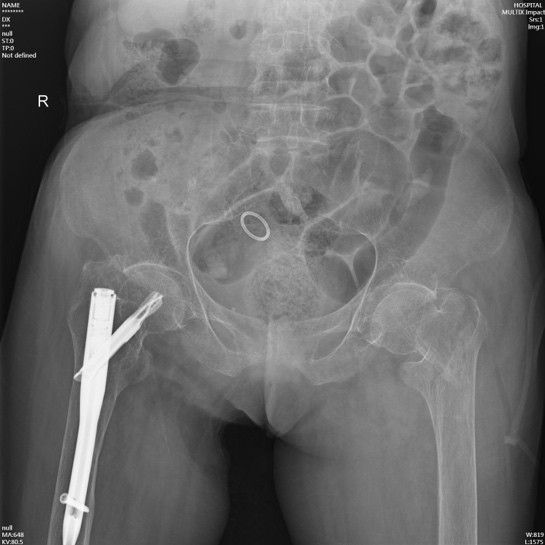

在询问陈奶奶的家属后得知,陈奶奶年事已高,疾病缠身,除了有冠心病、心房颤动、全心衰等心脏方面的问题,同时合并有老年性骨质疏松、主动脉硬化、甲状腺功能亢进(未进行治疗)、贫血、凝血功能异常等基础疾病。另外,陈奶奶曾于2020年在黄播 顺利完成了“右侧股骨粗隆间骨折闭合复位APFN内固定术”,术后恢复良好,3年来生活基本恢复正常。

入住黄播 骨伤科后,钟水林主治医师立即安排陈奶奶完善各项术前检查。考虑到陈奶奶高龄同时合并有较多的基础疾病,有些疾病并未系统规范治疗,如甲亢疾病;围手术期风险较大,我科组织全院大会诊:邀请心血管科、内分泌代谢病科、重症医学科、麻醉科等进行术前讨论和评估;结合患者病史,评估患者病情,充分讨论后,钟水林主治医师与陈奶奶家属进行了充分沟通,为其量身定制了最佳的治疗方案,对其骨折采取微创闭合复位手术治疗(APFN)。

手术在病人骨折后第三天实施,手术当天在麻醉科王翔峰主任团队的紧密协作,修忠标主任医师的指导下,钟水林主治医师和韩海医师顺利地完成了手术,手术总共耗时30分钟。